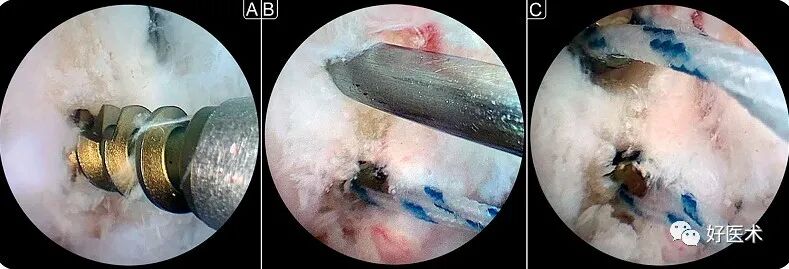

图片上图为关节镜下Broström术式治疗慢性踝关节不稳,关节镜辅助下在外踝部置入两枚带线锚钉,两锚钉之间距离约0.5cm(来自参考文献5)

图片

上图为关节镜下行外侧韧带修复术治疗慢性踝关节外侧不稳症。A:在腓骨尖植入锚钉;B:理好锚钉线准备缝合距腓前韧带;C:缝合钩缝合距腓前韧带。(来自参考文献7)